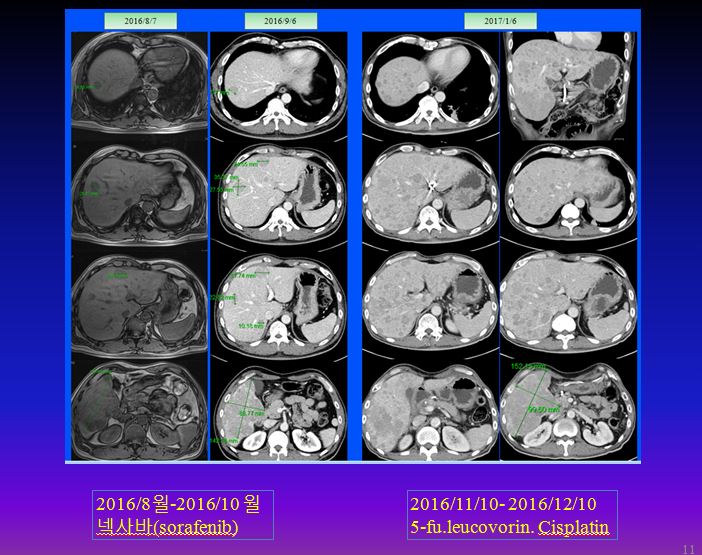

이후 8월 7일 MR상 거의 간의 우엽에 14cm 가까이 되는 종양이 보이는데 그 사이에 암이 3cm 이상 자랐다는 이야기가 된다. 이후 K 의료원에서 넥사바라고 불리우는 sorafenib을 2달 동안 사용하였다. 이후 결과는 간의 종양은 약간 자랐다고 볼수 있고 간암의 수치는 많이 떨어졌다고 하였다.

가족들은  간암의 수치가 좋아져서 간의 종양도 많이 줄었을 것으로 기대하였으나 크기는 오히려 약간 커지는 경향을 보이자 많이 실망을 하였고, 이후 주치의는 소음인약인 5-fu. leucovorin.cisplatin 등 folfox 공식을 사용하여서 2016년 11월부터 12월까지 한 달간을 사용하였다.

이후 주치의는 folfox 공식에 준하는 cisplatin 5-fu. leucovorin을 결합 사용하였는데 이는 모두 소음인 약물로 소음인에게는 유효하지만 태음인에게는 반응을 하지 않거나 더 빨리 암을 진행시킬 수있다. 암은 유지시키는 것만으로도 중요한데 암 크기가 다소 늘어났다고 하여서 소음인 약으로 바꾸고 나서 결국은 매우 악화되어서 며칠 전 본원에 내원하였다. 이를  비교해 보면 다음과 같다.

9월 사진만 해도 약간씩 증가된 것으로 보이는데 한 달간 소음인 약물로 추론되는 항암제를 사용하고 나서 간 전체가 무수히 많이 보이는 점들로 꽉 차게 되었다. 여기다가 또 무슨 약침이니 하는 요법을 하는 도중에  본원에 내원하게 되었다. 환자는 나이가 아직 젊다는 것 빼놓고는 무엇하나 건질 것이 없는 정도로 상태가 나빴지만 어느 한의사 선생님이 소개해 주어서 내원하였다 한다.

아래의 그림과 같이 folfox  3차에 다발성으로 전간에 작은 nodule들이 퍼지는 것을 볼 수 있다.